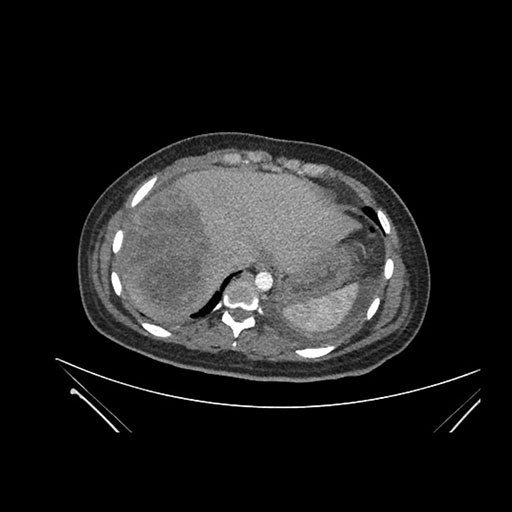

Imaging Analysis

Look through the patient's CT scan to identify any areas of concern for the necessary procedure.

Axial Venous